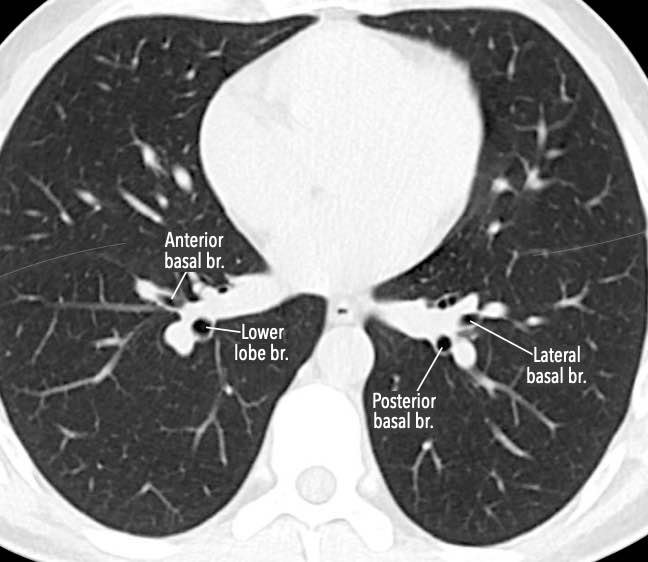

Phế quản trên CT

Cuộn qua các hình ảnh để quan sát khí quản phân chia thành phế quản chính phải và trái, sau đó tiếp tục phân chia thành các phế quản thùy và phế quản phân thùy.